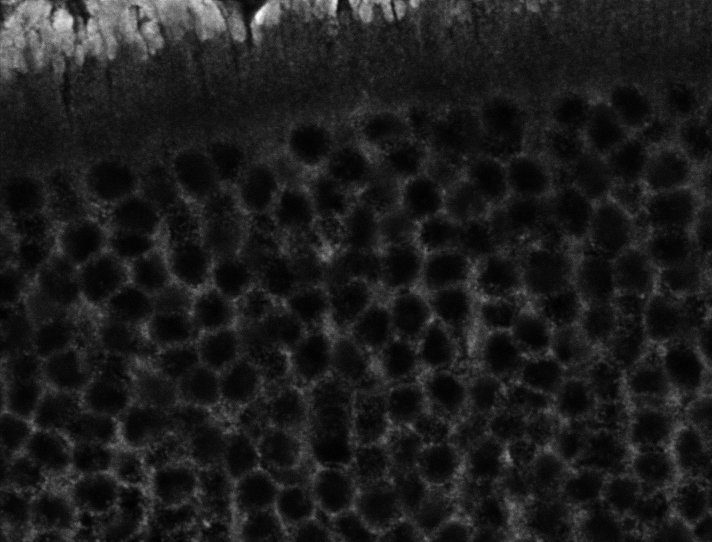

Healthy Choroid

Unhealthy Choroid